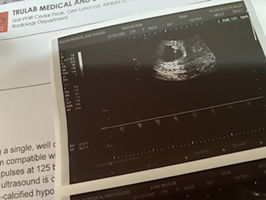

Hi mi, much better kung magpacheck po. Any bleeding is threatend miscarriage as per my OB. Nagpa ultrasound na po ba kayo?